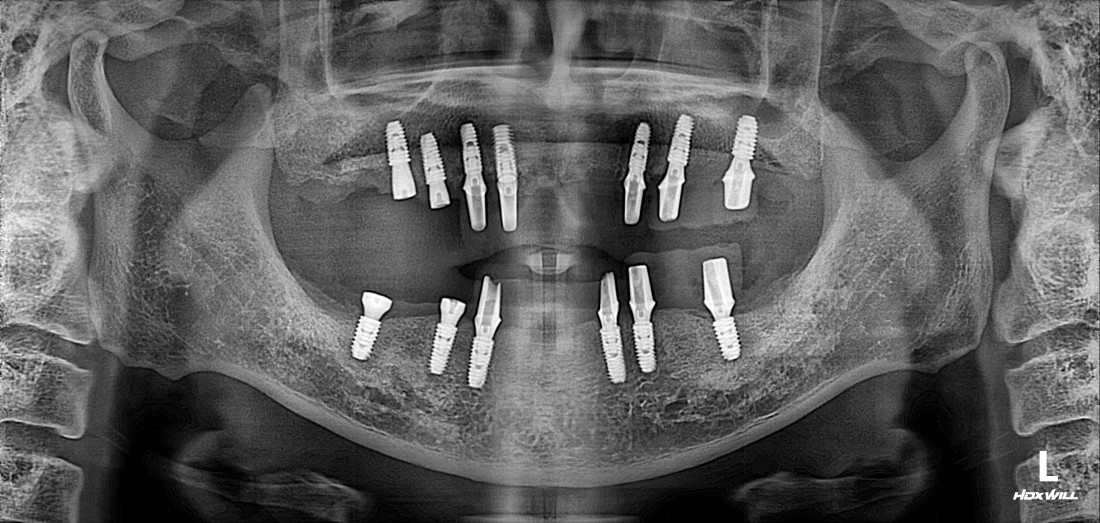

광주 전체임플란트에서는

신경쓰이는 앞니 임플란트도

예쁘게 제작합니다

무엇보다도 전체임플란트 중에서

특히 앞니임플란트가

자연스럽고 예쁘게 완성이 되는지

많이 걱정하실텐데요.

광주 전체 임플란트 치과는

4층 자체 치아기공소를 운영하여

보철물 퀄리티를 최상으로 유지합니다.

자연치아보다 더 자연스럽게,

더 잘 씹어질 수 있도록

심미적인 요소와 기능적 요소를

모두 고려하여 제작하고 있으며

불편함이 생기시면 바로 수정이 가능하기 때문에

번거로움 없이 광주 전체임플란트를

완성할 수 있습니다.